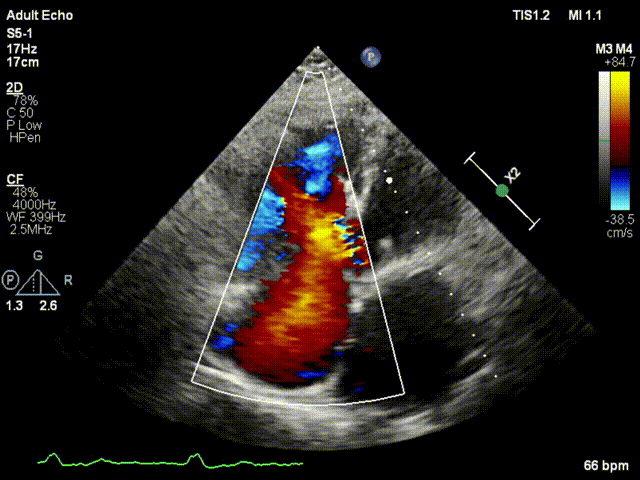

本次接受治療的患者是一名74歲的女性,14年前因風(fēng)濕性心臟病行二尖瓣生物瓣植入術(shù),合并房顫。近3年來反復(fù)因腹脹、納差、下肢水腫入院,藥物治療欠佳。心臟超聲顯示三尖瓣極重度反流(有效反流口面積:0.76cm²,反流容積:79ml),繼發(fā)性右房室增大及上、下腔靜脈增寬(右房上下徑*左右徑:52*41mm,右室左右徑:46mm,下腔靜脈:29mm),右室收縮功能正常,肺動(dòng)脈收縮壓 43mmHg,左心室射血分?jǐn)?shù)73% ?;颊呒韧_胸手術(shù)史,術(shù)前評(píng)估STS 評(píng)分為7.02分,CRS 9分,無法接受體外循環(huán)下三尖瓣外科手術(shù)。面對(duì)這一傳統(tǒng)治療無法解決的困境,葛均波院士及其團(tuán)隊(duì)周達(dá)新教授、潘文志教授、張?jiān)床┦俊㈥惿┦考靶某业呐舜湔浣淌?、李偉教授?jīng)過討論決定,采用創(chuàng)新的Lux-Valve Plus系統(tǒng)為患者進(jìn)行經(jīng)血管三尖瓣置換。

手術(shù)在患者全麻狀態(tài)下進(jìn)行,采用經(jīng)右側(cè)頸靜脈作為入路,將裝載有人工瓣膜的輸送器緩慢推送至右心房;并在經(jīng)食道超聲和DSA的引導(dǎo)下小心調(diào)整輸送器角度,將輸送器送入右心室;逐步釋放瓣膜錨定裝置和盤片,調(diào)整瓣膜位置后,錨定瓣膜完成植入。術(shù)后右房壓明顯下降,從術(shù)前的25/10(16) mmHg降至術(shù)后即刻的12/7(10) mmHg,術(shù)后超聲提示人工三尖瓣同軸性良好,固定牢固,無反流及瓣周漏,手術(shù)室即刻拔除氣管插管。